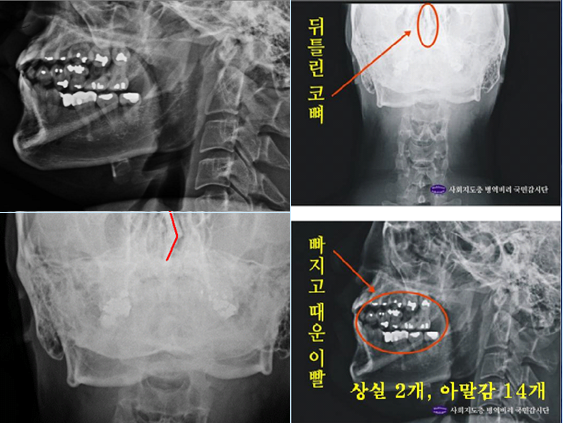

주신씨 구외 X-Ray 사진을 보면, 치아 상태가 매우 불량하다는 사실을 알 수 있다. 치아 2개는 아예 없고, 아말감으로 때운 치아가 무려 14개에 달한다.

- ▲ ▲ 박주신 엑스레이(X-RAY) 분석사진. ⓒ 뉴데일리DB

치과의사 문모 씨는 2005년 8월과 2008년 11·12월 박주신 씨의 치아를 치료한 사실이 있다면서, 치아 X-Ray와 관련돼 피고인들이 제기한 의혹을 전면 부정했다. 치과의사 문씨는 자신이 박주신씨의 치아 14개를 아말감으로 치료했다면서, 건강보험공단으로부터 보험급여를 받았다는 ‘보험급여신청 관련 자료’도 제출했다.